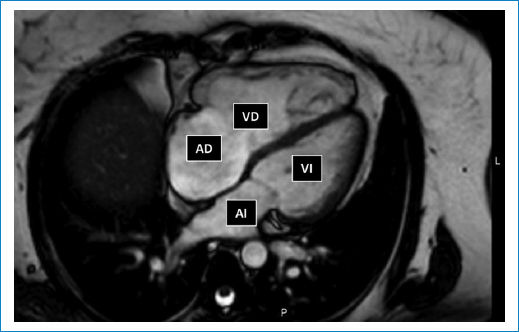

La FE fue menor en HP (control 64 ± 2% vs. HP 52 ± 5%; p < 0,05). La figura 2A muestra imágenes de cuatro cámaras en un paciente del grupo control y uno del grupo HP donde se puede observar la dilatación del VD en el paciente HP. El grupo HP presentó mayor VTD y VTS (Fig. 2B). Estas diferencias se mantuvieron al indexar los volúmenes (Fig. 2C). En HP, el aumento de VTD fue menor que el de VTS (VTD 70 ± 9% respecto a control vs. VTS 152 ± 36% respecto a control; p < 0,05). Esta diferencia se hizo más evidente al indexar los volúmenes a la superficie corporal (VTD indexado 63 ± 11% respecto a control vs. VTS indexado 183 ± 44% respecto a control; p < 0,001).

Interrelación VD/VI

En el grupo control, en el VD se mantuvieron similares los valores de VTD (104 ± 9% respecto a VI; p = 0,18) y VTS (111 ± 12% respecto a VI; p = 0,15). Sin embargo, en el grupo HP estos valores incrementaron en el VD: VTD (160 ± 9% respecto a VI; p < 0,001) y VTS (223 ± 33% respecto a VI; p < 0,001). Estas diferencias observadas en HP se mantuvieron al indexar ambos volúmenes.

En el grupo control, la FE del VD se mantuvo en valores similares que el VI (97 ± 3% respecto a VI; p = 0,26) pero en el grupo HP la FE del VD estuvo disminuida (82 ± 9% respecto a VI; p < 0,05).